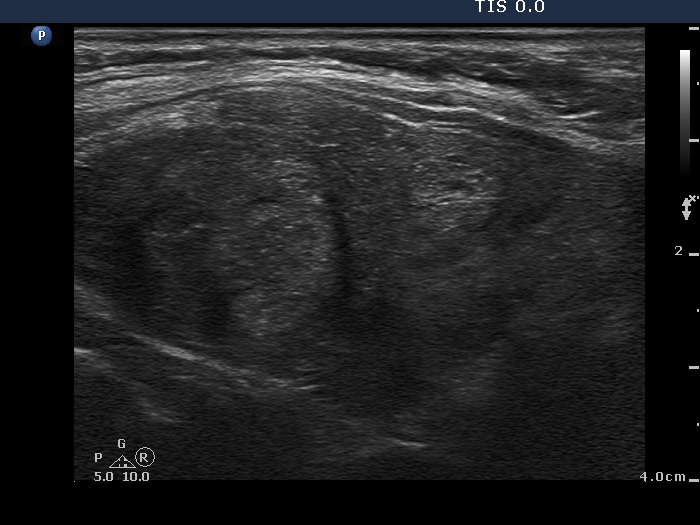

Follow-up investigation 11 months after the initial one (fourth row of images):

Clinical presentation. The original complaints of the patient recurred including 3 kg loss in weight and tachycardia.

Palpation: unchanged.

Results of blood tests: hyperthyroidism (TSH undetectable, FT4 47.5 pM/L) on daily 10 mg methimazole.

Ultrasonography. The degree of hypoechogenicity and vascularization increased compared with previous investigation.

The dose of the methimazole was increased to 20 mg.